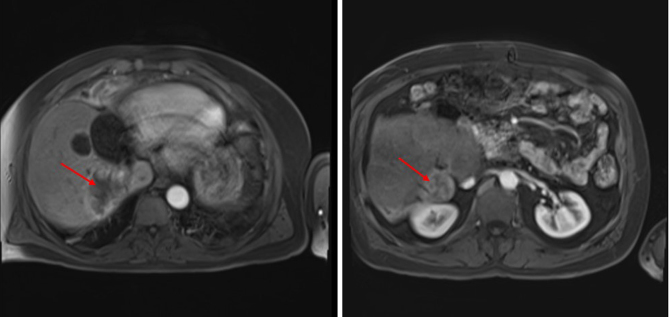

Selective internal radiation therapy (SIRT) is a novel intervention for both primary and metastatic malignant liver lesions. Adrenocortical carcinoma (ACC) is rare with limited treatment options; evidence for SIRT in ACC liver metastases consists of case reports only. Selective internal radiation therapy (SIRT) was employed to treat recurrent liver metastases in a 49-year-old gentleman with ACC, who previously underwent a left-sided hepatectomy. The patient opted for SIRT after reviewing the literature regarding mitotane chemotherapy and its toxicities. Selective internal radiation therapy (SIRT) provided several months of progression-free survival (PFS), with no toxicity and an excellent radiological response. The patient re-presented 12 years after the initial diagnosis with skeletal metastases and sadly died in September 2022. Substantial unmet need exists for effective treatments in ACC, with 75% of patients presenting with incurable disease. Developing widespread disease, SIRT offered 2 years' PFS in our patient; this was well tolerated with minimal residual liver impairment. Its use in ACC liver-limited disease warrants investigation.

Significance statement: Adrenocortical carcinoma (ACC) is a rare and aggressive tumour with limited treatments. Once metastatic disease develops, existing standard-of-care treatments offer a dismal overall survival, alongside marked toxicities. Selective internal radiation therapy (SIRT) may represent a new intervention in the treatment paradigm for liver-limited, metastatic ACC. Here, we present the case of a patient treated with multiple rounds of SIRT for relapsed, liver-limited ACC, prolonging survival by several years. Recurrent SIRT led to maintained liver function and no toxicities. Little evidence outlines its use in ACC but further study is certainly warranted to ascertain the value of SIRT, considering the limited treatment landscape that currently exists.